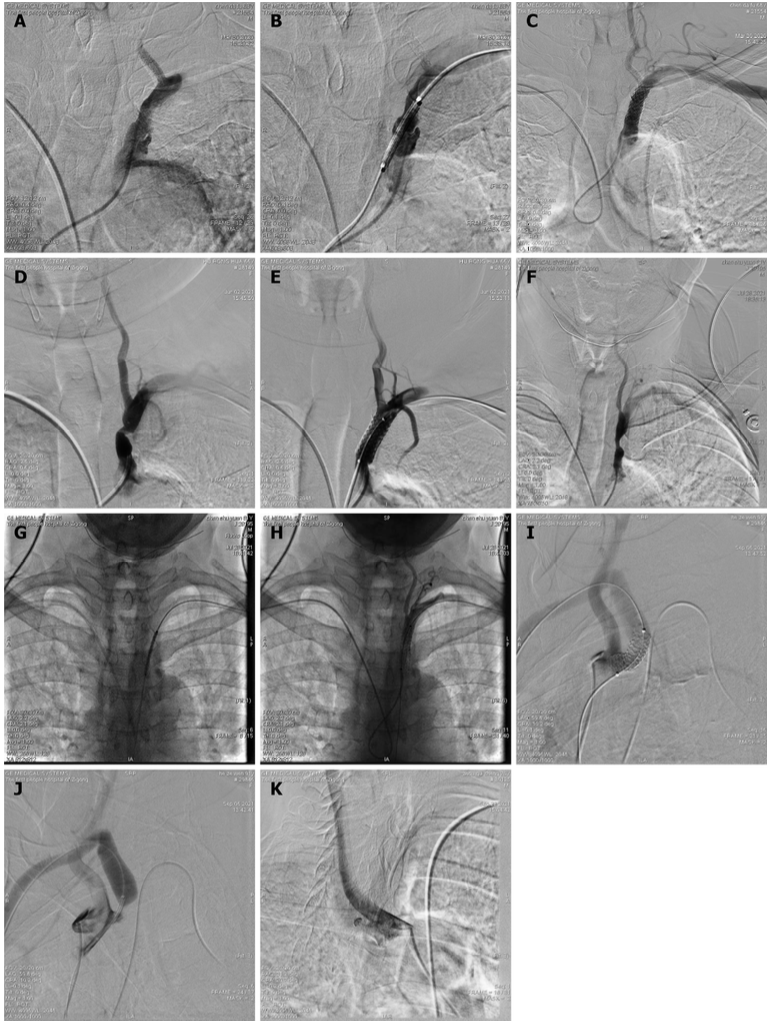

· 动脉鞘连接压力传感器,支架前双侧动脉压对比(左/右)

· 10-29mmOminiLink支架

▪18导丝送入18系统球囊预扩;

▪送入10-29mmOminiLink支架;

▪支架植入及植入后造影

支架覆盖理想,狭窄解除。

· 术后造影确认盗血消失,动脉压测量双侧对比(左/右)